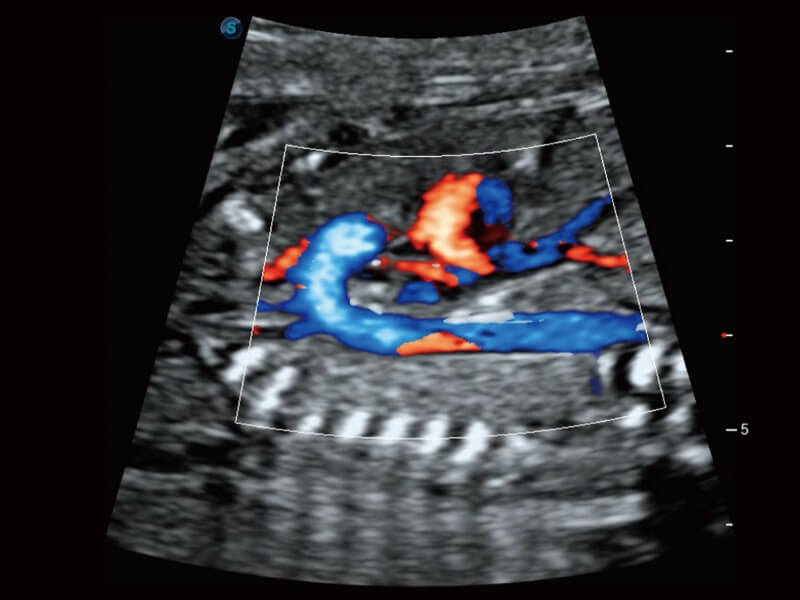

Die Anpassung der Bildparameter erfolgt nun nicht mehr mühsam. Auto B/C hilft dabei, die Bildqualität unter B- und Farbdoppler-Modus mit nur einem Klick zu optimieren. Mehrere Parameter wie Gain, TGC, ROI-Position, Lenkwinkel usw. sind in dieser vollautomatisierten Methode enthalten.